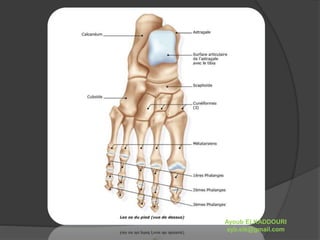

 Le pied contient 26 os en moyenne.

 Il est composé de 3 éléments principaux :

 le tarse, dont les os comprennent :

 le calcanéum, qui compose le talon,

 l'astragale sur laquelle s'appuient les os de la

jambe (tibia, fibula),

 les os cunéiformes,

 et le scaphoïde.

 le métatarse (composé de 5 os),

 les phalanges : os des orteils.